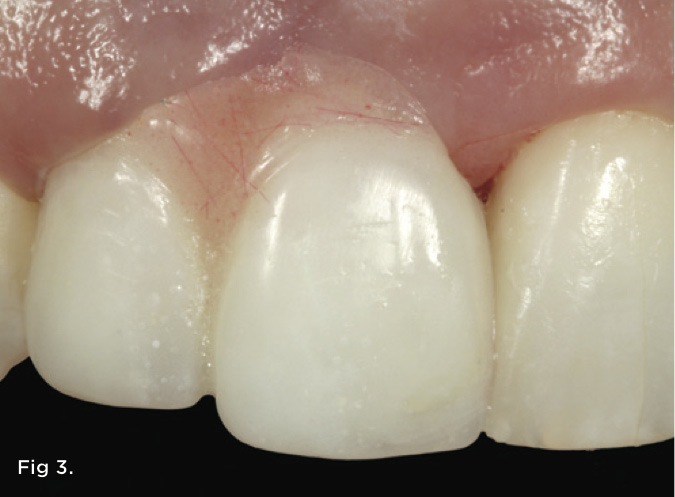

Fig 3. Artificial gingiva (pink autopolymerizing acrylic resin) was used to replace the lost papilla height. This served to communicate to the patient the visual endpoint of treatment as well as how much orthodontic eruption would be required to correct the defect.

Figure 3

A 38-year-old Caucasian female patient presented with a high smile line and loss of the papilla between tooth No. 7 and edentulous adjacent site No. 8 (Figure 1). Understandably, the patient was unhappy and embarrassed about her esthetic condition. Her dental history revealed tooth replacement of No. 8 with an implant that eventually failed. The site had been previously bone grafted upon implant removal. She was given a composite pontic No. 8 bonded to a tooth No. 7 composite veneer as a transitional restoration. The implant was positioned too close to the proximal surface of tooth No. 7, which stripped the periodontal attachment of the root and ultimately caused loss of the papilla (Figure 2). As previously outlined, the treatment sequence would be to first provide a provisional restorative solution to evaluate the projected outcomes and assess if the patient was willing to undergo orthodontic therapy. In this situation, a full-coverage crown No. 7 with a cantilevered pontic No. 8, with artificial acrylic gingiva to replace the lost papilla on the mesial aspect of tooth No. 7 was used as a transitional temporary prosthesis (Figure 3). In addition, a composite resin restoration was placed on the mesial aspect of tooth No. 9 to restore its individual tooth proportion and shape. The patient’s esthetic outcome could now be evaluated with restorative correction alone; it was therefore mutually determined that the correction of her deformity would best be served with additional orthodontic forced eruption therapy. A fixed orthodontic appliance (brackets) was bonded to the teeth and temporary prosthesis. The level of the interproximal pink acrylic was used as a therapeutic guide for the amount of forced eruption required as well as the alignment of the mesial papilla of No. 7 to that of the adjacent papillae height (Figure 4). Floss was used to elevate the amount of vertical movement achieved relative to the adjacent papilla tooth No. 9. Eventually, all the artificial pink acrylic was removed. (Note that the distal papilla on tooth No. 7 also comes more incisal—in fact, it is slightly excessive at the endpoint of treatment [Figure 5]). However, the distal papilla and midfacial tissues of tooth No. 7 can be reshaped through clinical crown lengthening toward the end of treatment prior to definitive restoration, thereby restoring the proper papilla height-to-tooth ratio of 40%. After stabilization of tooth No. 7 for a minimum of 6 months post-orthodontics, an implant was placed in site No. 8. A papilla-sparing incision design was used for flap elevation (Figure 6), bone allograft was used to further augment the facial aspect of the ridge simultaneously with implant placement (Figure 7), and a resorbable membrane was used for guided bone regeneration.